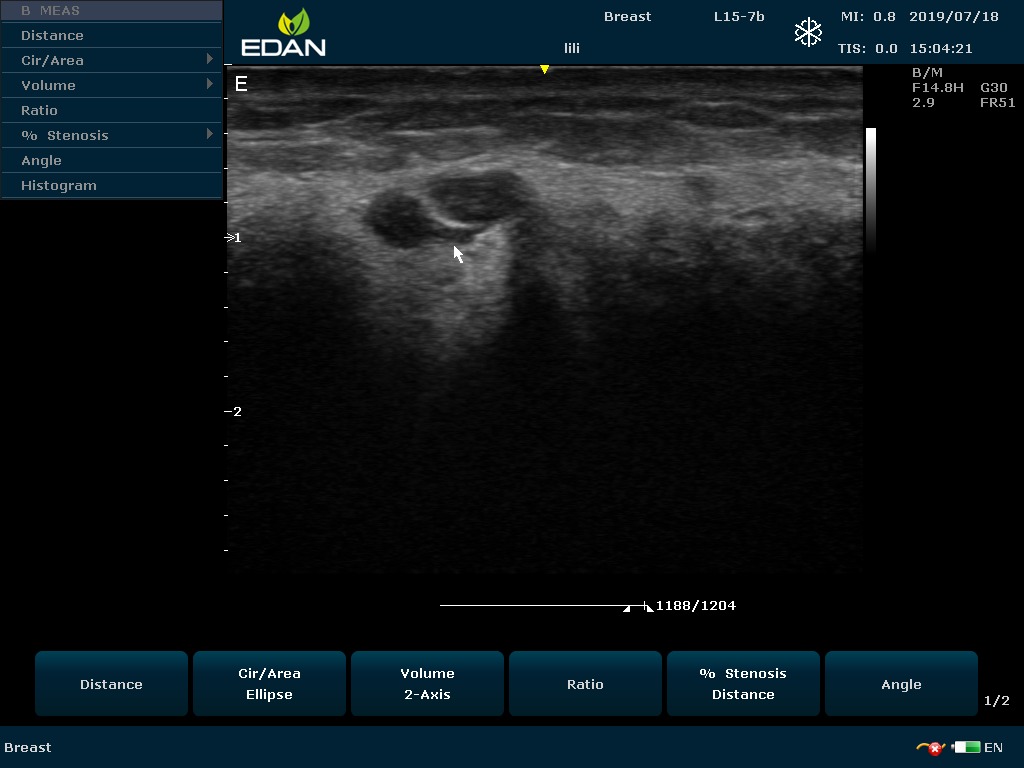

Особенность U60 Edan — расширенное применение. Ультразвуковой аппарат рекомендован для абдоминальных исследований, гинекологии и акушерства, кардиологии, педиатрии, урологии, изучения малых органов, сосудов. Для U60 Edan используются конвексные, линейные, фазированные и внутриполостные датчики.

Передовые технологии позволяют повысить качество визуализации в несколько раз. УЗИ-аппарат U60 Edan отличается возможностью быстрой настройки визуализации. Специальные функции позволяют моментально отображать данные за счет быстрой оптимизации параметров. Режимы визуализации: B-mode, M-mode, Color Doppler, Power Doppler Imaging, Pulsed Wave Doppler, Continuous Doppler.

Для улучшения качества изображений в В-режиме быстро регулируются все необходимые параметры. Быстрые инструменты изображения: LowFlow, Medium Flow, High Flow, Detail, Soft, High Contrast.